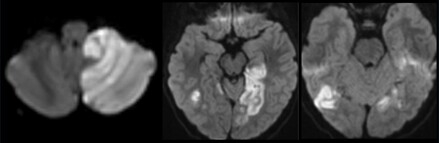

On hospital day 5, he became obtunded and was transferred to the pediatric intensive care unit with a new PCA stroke. He had additional bilateral posterior circulation strokes over the following days with new left posterior inferior cerebellar artery (PICA) occlusion, despite therapeutic heparin (Figure 2). On day 6, digital subtraction angiography (DSA) revealed bilateral vertebral artery dissections. As the left vertebral artery was more severely affected and the source of the left PICA occlusion, the left vertebral artery was sacrificed via transarterial coil embolization (Figure 3). On day 8, he underwent suboccipital decompression for cerebellar edema. On day 13, a DSA showed no compression of the right vertebral artery by neck movements, deeming bow hunter’s syndrome less likely (Figure 3). His previously placed EVD was replaced on day 14 with a ventriculoperitoneal shunt. Aspirin 81 mg was started on day 17. He was discharged on day 24 to inpatient rehabilitation with visual field deficits, bilateral arm weakness, and right-sided dysmetria.